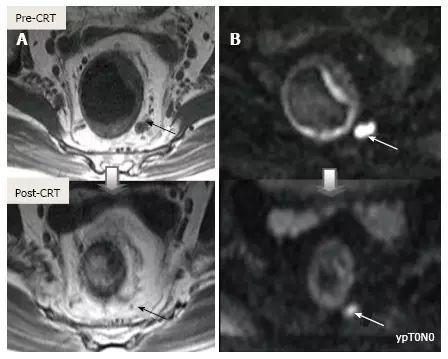

1.T 分期

采用传统 MRI 序列对 CRT 后肿瘤重新分期的精确性差于初始分期,尤其在证实完全缓解(yT0),主要是很难将残留的肿瘤与纤维化、水肿和正常粘膜区分开,因此 CRT 后正常的 2 层直肠壁提示为完全缓解,而残留纤维化既可以是肿瘤残留也可以是完全缓解(图 17)。

实际上 CRT 后 T2 加权 MRI 后上纤维化的信号强度很低,而残留肿瘤区域则为中等强度,仔细评估高分辨图像和 DWI 是能区分小的残留病变和纤维化的(图 18)。

图片

图 17. 新辅助放化疗后肿瘤重新分期。在不同患者的 T2 加权 MR 图像上分别显示(上:治疗前,下:治疗后)。A. 在 ypT0 直肠肿瘤中,治疗后的轴位图像显示正常的两层直肠壁(箭头),对应完全缓解;B. 在 ypT3 直肠肿瘤中,治疗后的轴位图像显示正常的双层直肠壁(箭头)。这是 MR 评估完全缓解的假阴性例子;C. 在 ypT0 直肠肿瘤中,原有肿瘤区域治疗后呈现厚的、纤维化的低信号强度疤痕(箭头)。